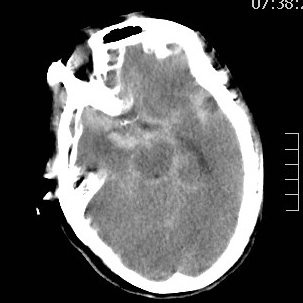

山东老年女性,2个月前遭遇颅内动脉瘤(一个血管上的不定时炸弹,不知道啥时候就爆炸了)破裂出血,病情危重。

动脉瘤经过多年修炼,形态奇葩,大动脉瘤上长着小动脉瘤,小动脉瘤上长着微小动脉瘤,还累及粗大的胚胎型大脑后动脉,经过一期单纯栓塞,消除了出血风险,老人家顺利出院康复。